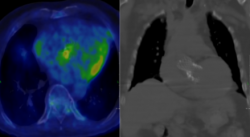

Az infekciózus endocarditis továbbra is komoly kihívást jelent a modern orvostudomány számára, magas morbiditási és mortalitási mutatóival még optimális kezelés esetén is.

A Heart Team rendszer mintájára 2023 januárjától elindítottuk az Endocarditis Team heti rendszerességgel működő multidiszciplináris referálási fórumát, amelyre minden szerdán van lehetőség.